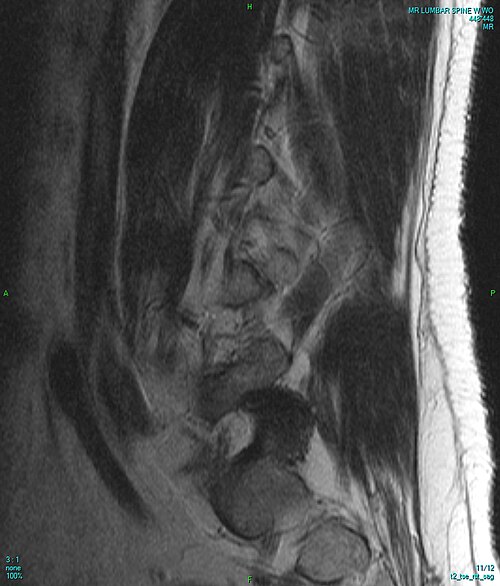

Normal lumbar spine phantom with healthy vertebral bodies, intact discs, spinal canal, and nerve roots

L4-L5 posterolateral disc herniation compressing the L5 nerve root with disc desiccation, annular tear, and...

Thoracolumbar compression fracture (T12) with vertebral body height loss, retropulsed fragment, marrow edema, and...

Lumbar spinal stenosis with ligamentum flavum hypertrophy, facet joint arthropathy, disc bulge, and narrowed central canal